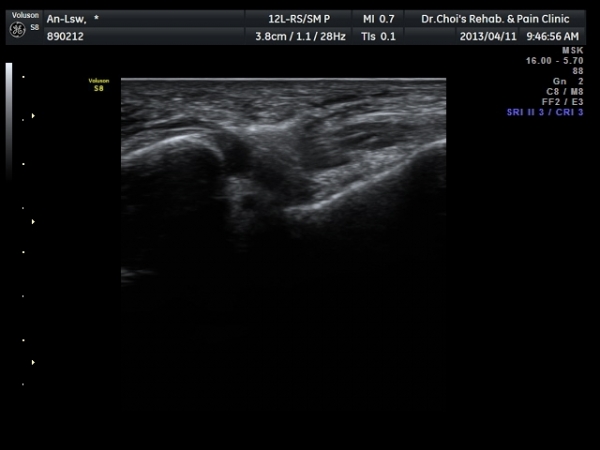

Àü°Å°ñºñ°ñÀδë Á¾´Ü¸é°Ë»ç»ó Àδë ÀδëÀÇ Àú¿¡ÄÚ ºÎÁ¾°ú(±×¸² 3)

ºñ°ñºÎÂøºÎ ¿¬°á¼º ¼Ò½ÇÀÌ °üÂûµÈ´Ù(±×¸² 4).

ÃÊÀ½ÆÄÅõ½ÃÇÏ ºÎÇϰ˻翡¼­ ºñ°ñ°ú ÀÎ´ë ºÎÂøºÎ¿Í ºñ°ñ°ú °Å°ñ »çÀ̰¡ ¹ú¾îÁø´Ù

(樨毢 1)

Àü°Å°ñºñ°ñÀÎ´ë ¼Õ»óÀÌ °üÂûµÇ´Â °æ¿ì ¹Ýµå½Ã ÃÊÀ½ÆÄÅõ½ÃÇÏ ºÎÇϰ˻縦 ½ÃÇàÇÏ¿©

ÀδëÀÇ ¿ÏÀü ÆÄ¿­·Î ºÒ¾ÈÁ¤¼ºÀ» º¸ÀÌ´Â °æ¿ì 3ÁÖ ÀÌ»ó ¼®°í°íÁ¤ÀÌ ¹Ù¶÷Á÷ÇÏ´Ù.